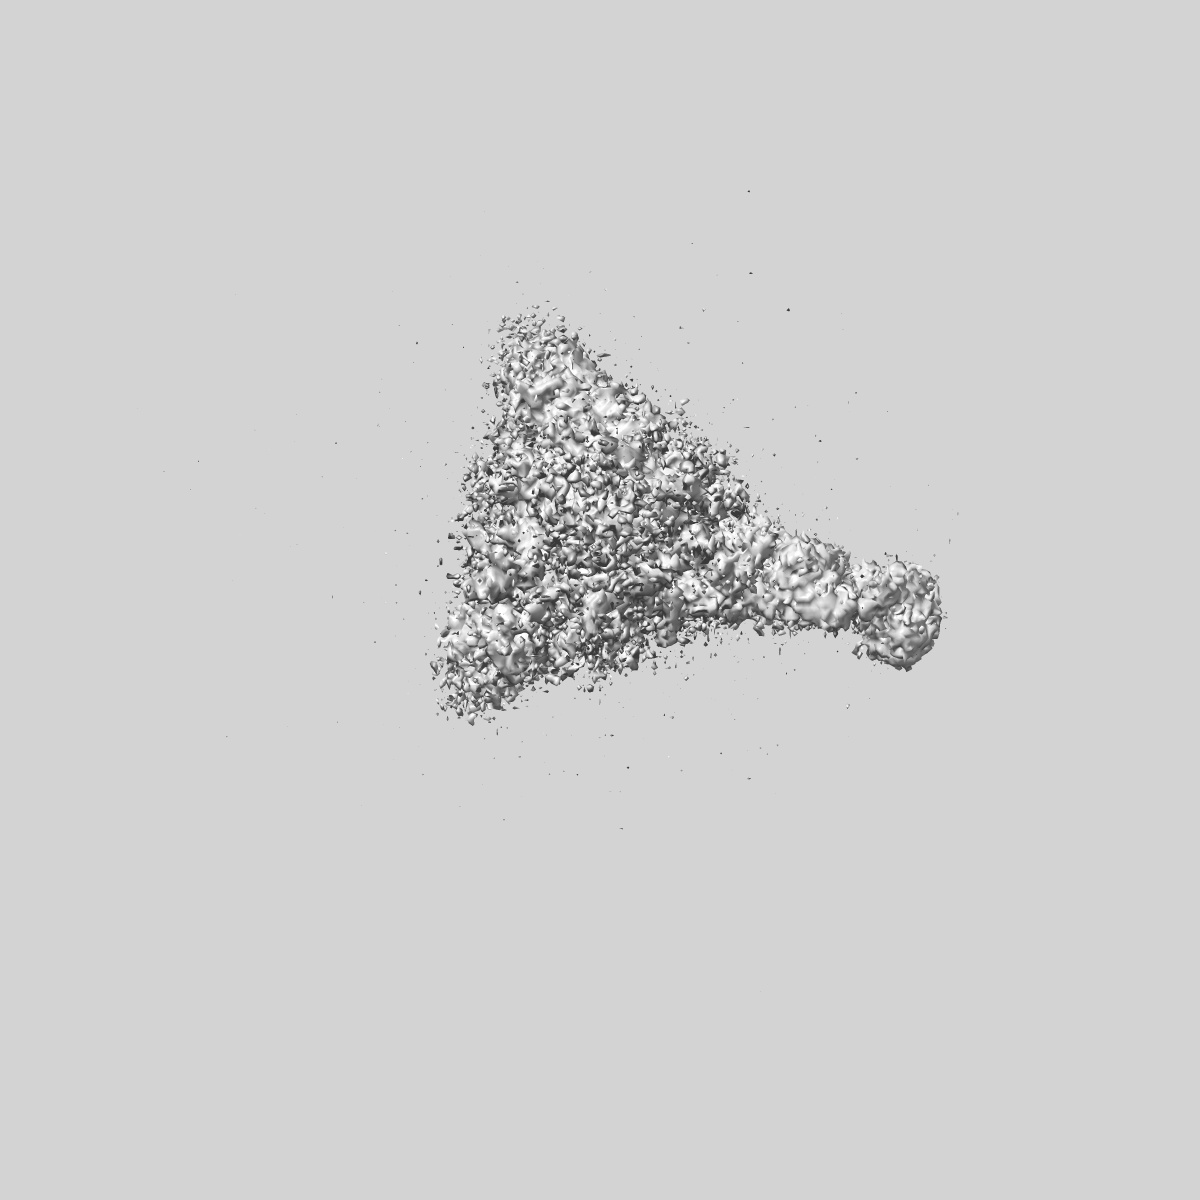

SARS-CoV-2 Wuhan Spike ectodomain in complex with NHP polyclonal antibody NVX-NHPSA5 (NVX-CoV2373/rS-Beta immunized)

Single-particle4.5 Å

Sample: SARS-CoV-2 Wuhan spike ectodomain in complex with NHP polyclonal antibody NVX-NHPSA5